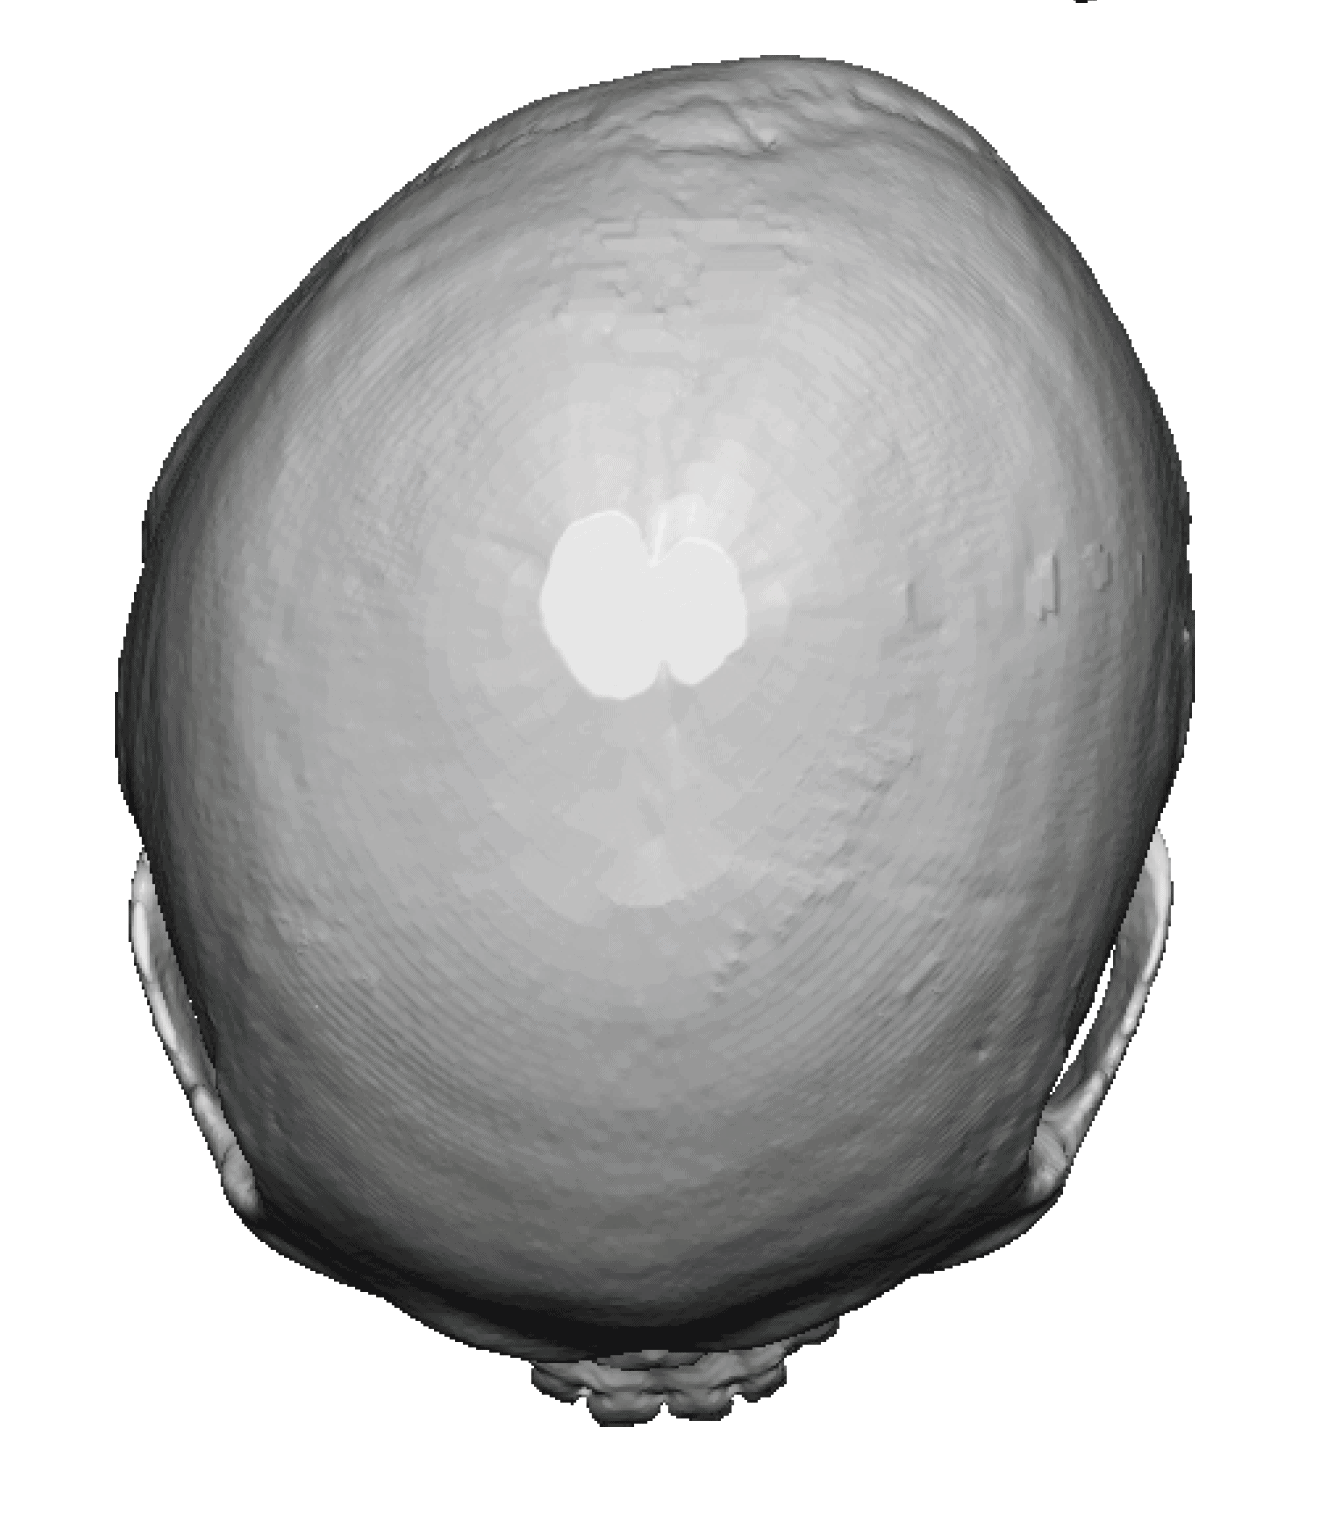

Desire for head shape asymmetry improvement as the final stage of total skull reshaping surgeries. (previous skull implants are in green color)

Placement of custom temporal implant through an incision behind the ear.

Desire for head shape asymmetry improvement as the final stage of total skull reshaping surgeries. (previous skull implants are in green color)

Placement of custom temporal implant through an incision behind the ear.